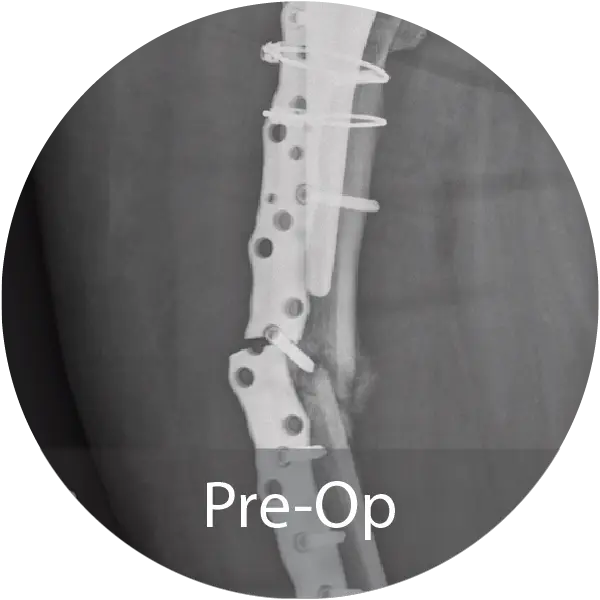

Case of an 81-year-old female with a periprosthetic femoral non-unionfracture and failed hardware treated with repeat ORIF and NMP fibers hydrated with saline. Progressive callus formation on x-ray and patient reported no pain and full range of motion 1 year post-op.